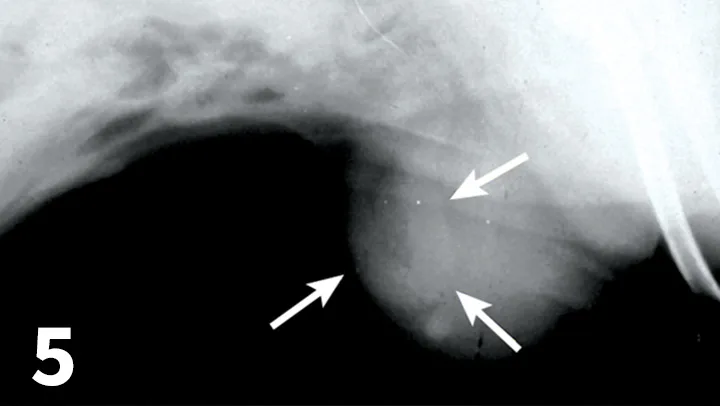

FIGURE 5

Lateral radiographic view showing tubular organ displacement into the subcutaneous tissues (arrows) from a ventral incisional hernia.

Imaging

• Plain films showing abdominal organ displacement into subcutaneous tissue at the wound site are diagnostic for an incisional hernia (Figure 5).